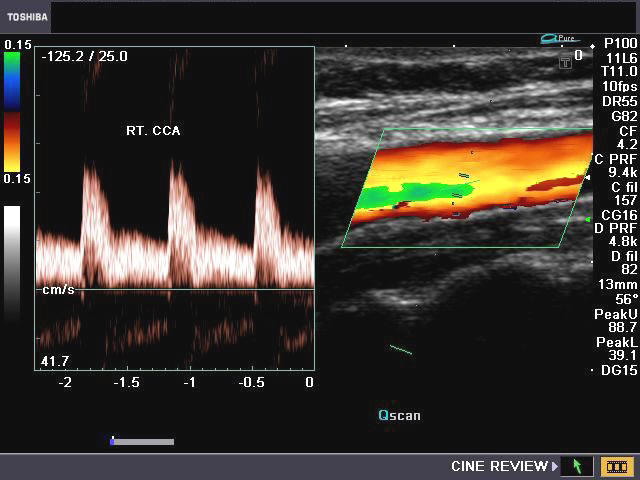

The above images (Rt. CCA) show moderately broad systolic peaks and moderate diastolic flow in diastole. The peak systolic velocity (PSV or V-max) is also in a range between that of the ICA and ECA. This is the typical appearance of the waveform of the CCA. Normal PSV for the CCA is usually less than 100cms./sec. (In this case, the PSV= 94 cms./sec.). The PSV in the CCA increases towards its proximal part (ie: towards the aorta).